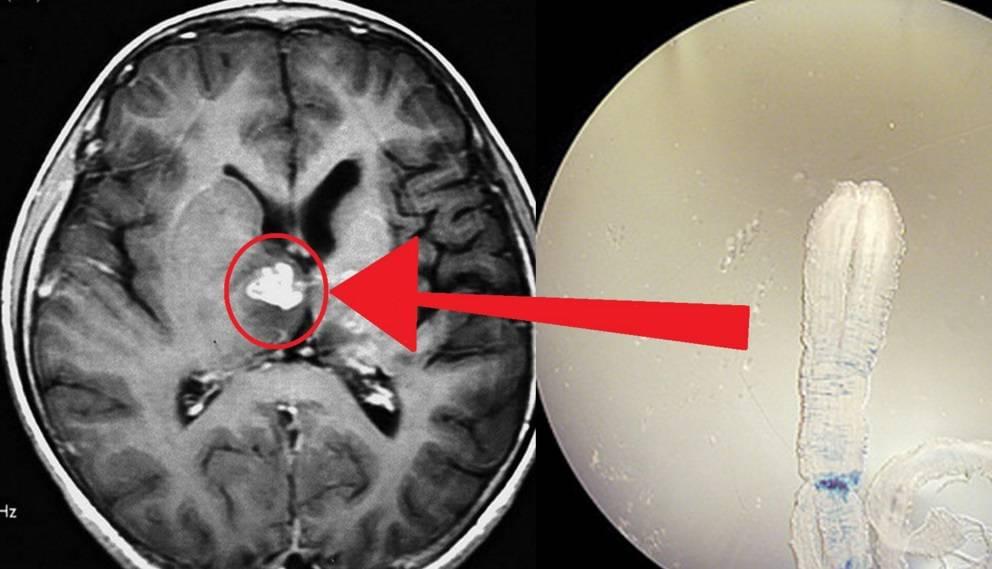

Още един случай, който шокира дори мен. Мозъкът на 49-годишен пациент е напълно покрит с паразити и техните ларви. Причината за смъртта е исхемичен инсулт. Но това е само предположение! В действителност паразитите просто се хранят с човешка мозъчна тъкан и я изяждат жива! Пациентът през целия си живот страда от главоболие, нарушения на съня и паметта. След това, когато достатъчно големи участъци от мозъка бяха увредени, се добави епилепсия. Пациентът почина шест месеца по-късно.

Паразити, извлечени от различни човешки органи.

Паразити, извлечени от различни човешки органи.